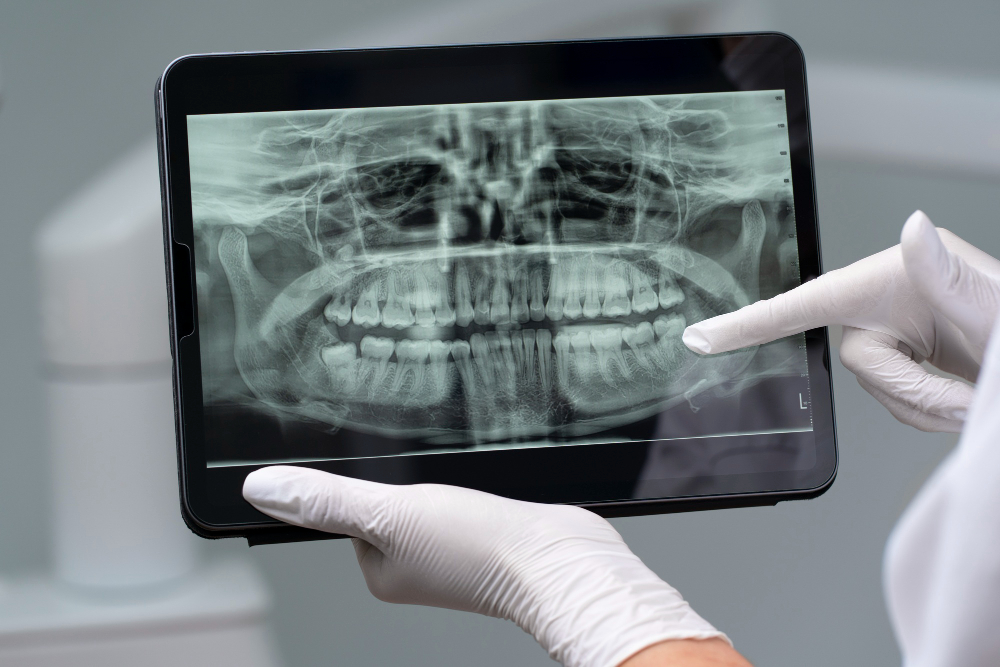

X-Rays are used to examine the inside of your teeth. We are hoping to be able to catch any problems that we can’t see with the naked eye! Using radiology, we are able to see which teeth are developing cavities. We may also see some teeth or gum areas that may require some extra work.